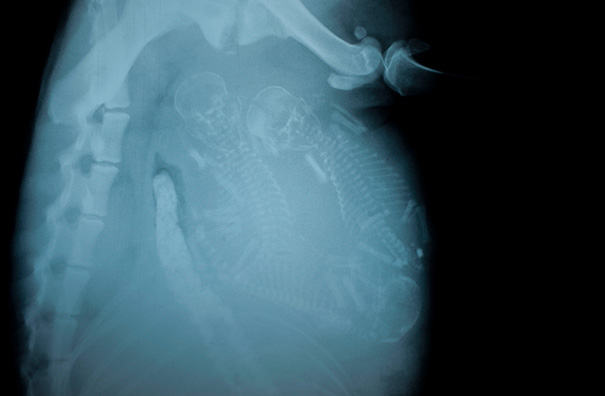

Pregnant Dog X-Ray

These are easier to see then the preg kitten. Looks like a lot of pups in there!

I hope I can't count. There's more puppies then she'll have teats to feed them.